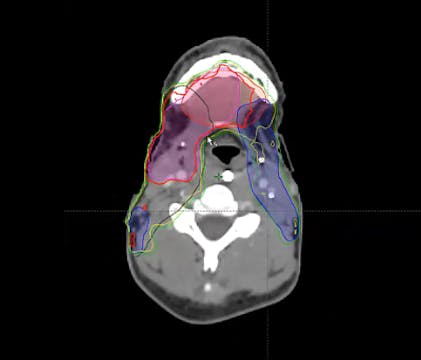

keep esophagus off 2 cm, 4-5 field VMAT, push a lot harder, omit level 6, PTV, 15 Gy, bilateral tongue, node positive, post-op tonsil, 60 Gy margins, negative margins, chemoradiation, ipsilateral neck, cisplatin, T2N2, tonsillectomy, left neck dissection, SCC, CTV, uvula, soft palate